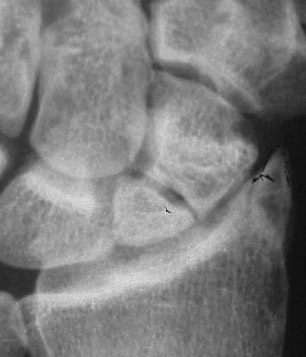

This X-ray shows a scaphoid nonunion.  The scaphoid fracture has never healed properly and now is not able to heal on its own.  This can often cause quite a bit of dysfunction in the wrist and will need to be treated.